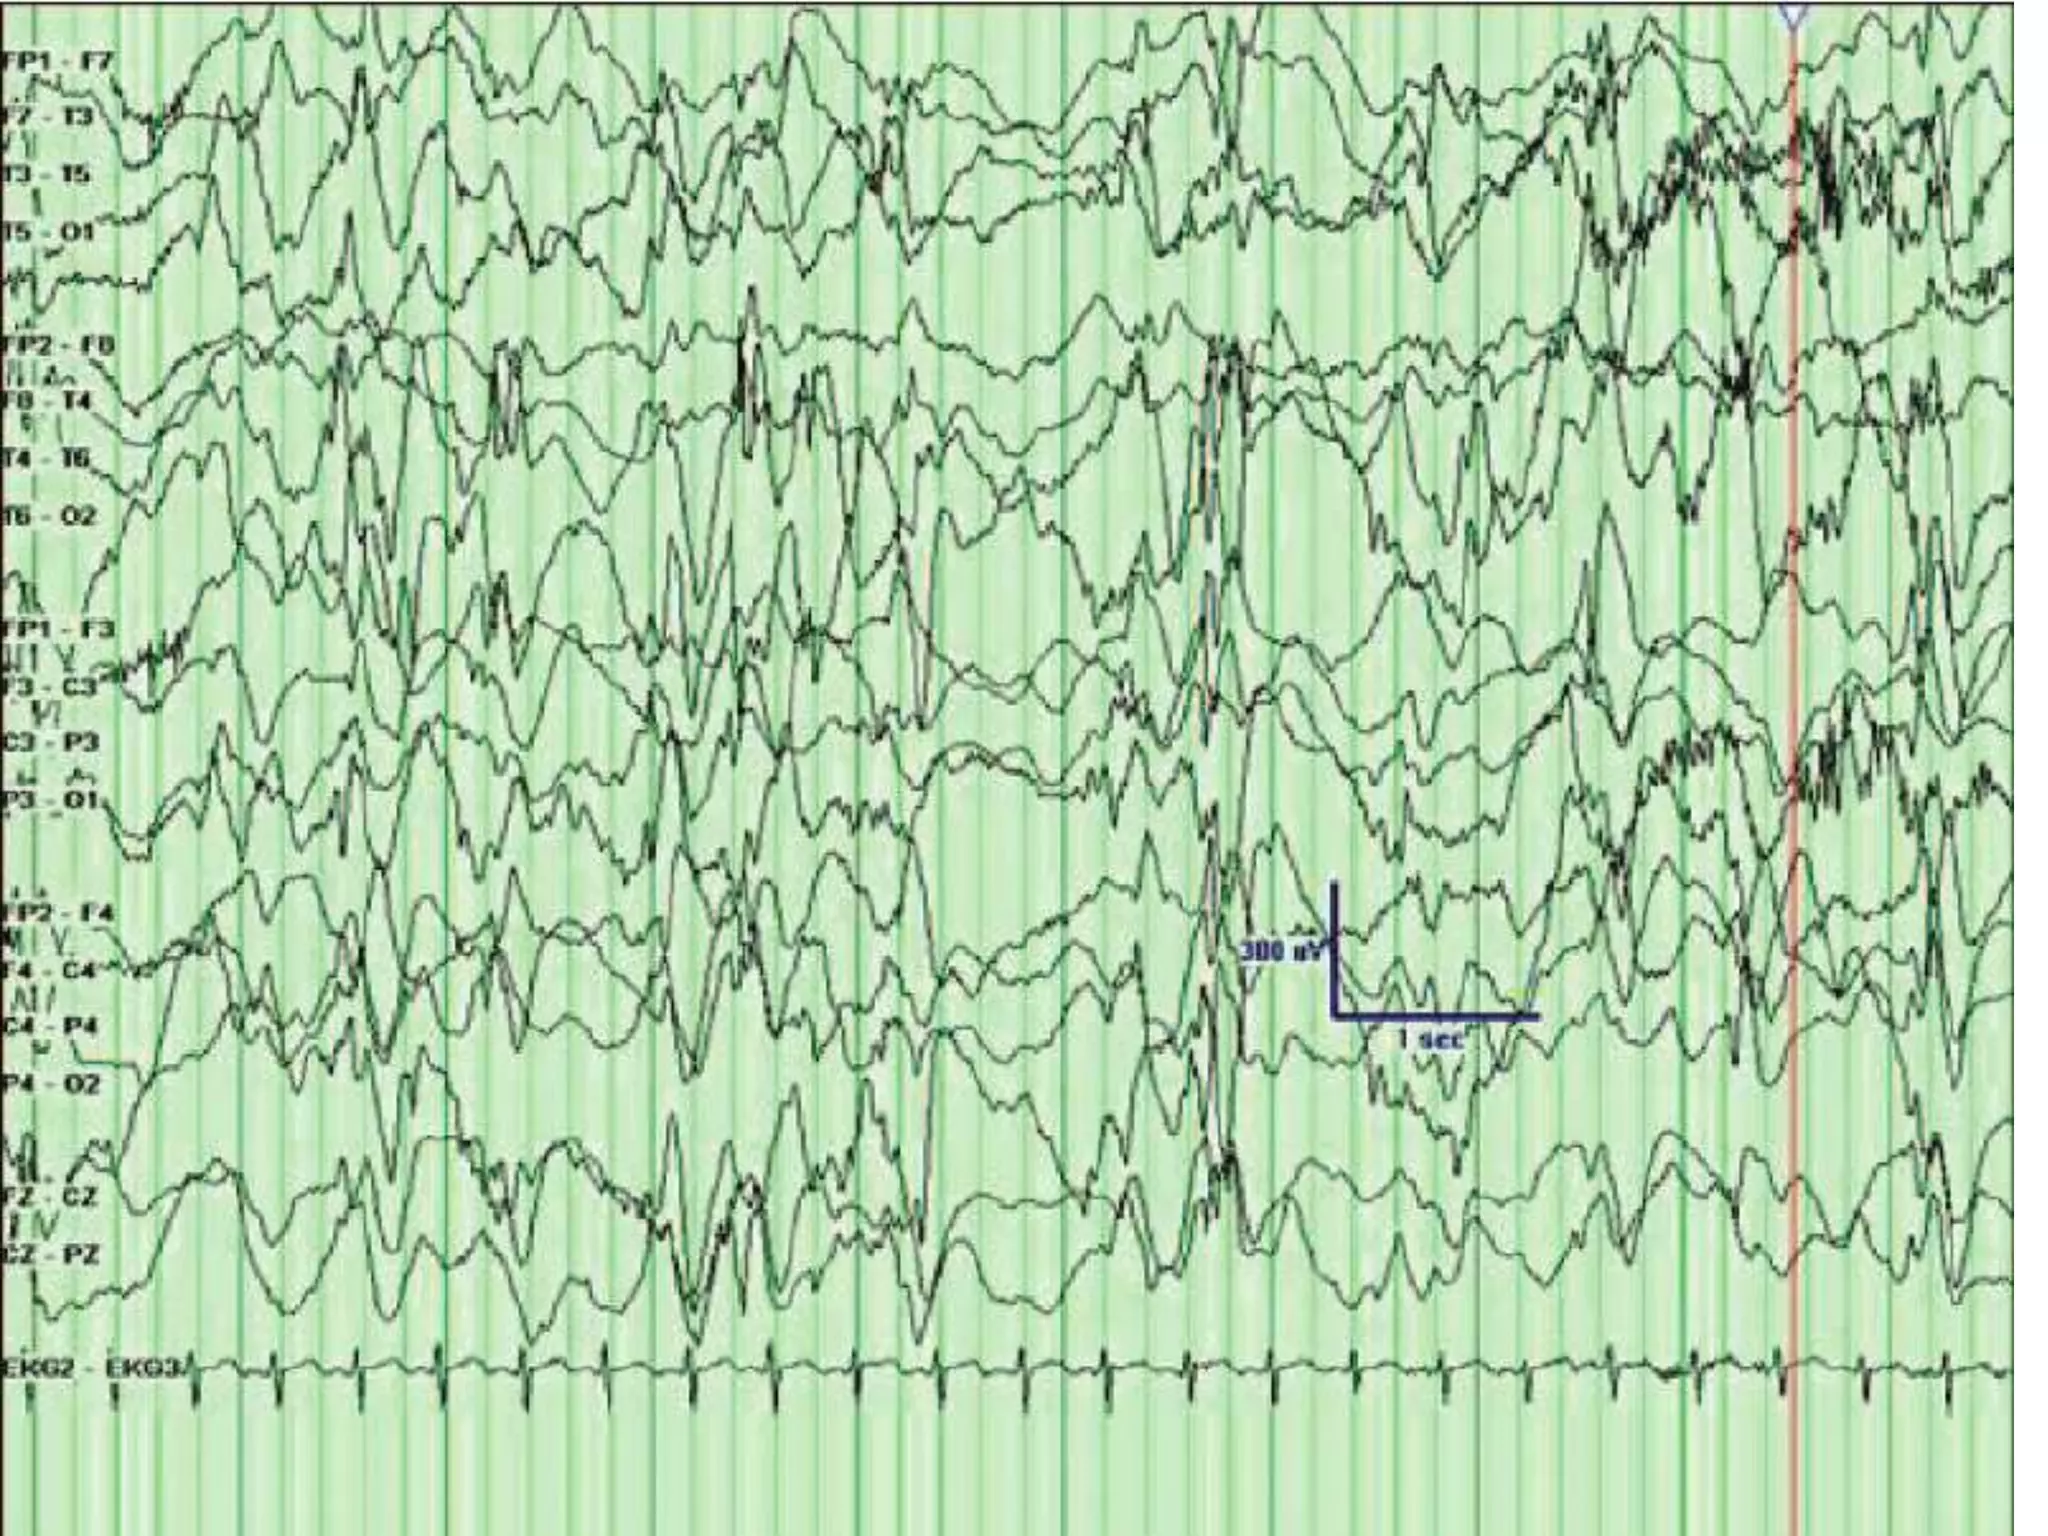

HYHPSARRYTHMIA

• Hypsarrhythmia is an abnormal pattern, consisting of

high amplitude and irregular paroxysmal sharp wave,

spike, poly spikes, independent, multifocal and focal

spike on all cortical region with a background of chaotic

(disorderly) and disorganized activity

• It is a pattern seen in patient with infantile spasm

• Hypsarrhythmia is frequently found in patients with

West syndrome .

• Appeared at the age of 4-6 or 13 months.

• Clinically patient is mentally and physically retarded.

• Also diffuse slowing is present.